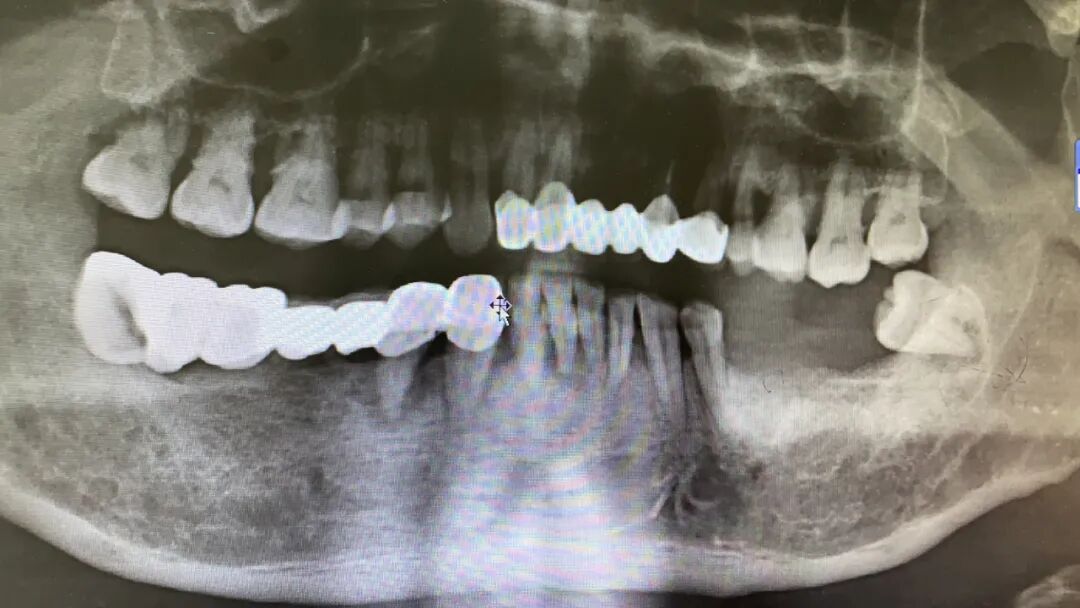

該患者全景片

王俊文副主任醫(yī)師接診了程先生,對(duì)其進(jìn)行了??茩z查:頜下區(qū)腫起,脖子腫大,咽喉腫痛,張口受限,說(shuō)話及飲食困難,33-41牙體Ⅲ°松動(dòng),叩(++),探(±)牙齦紅腫,牙周有膿液溢出,頜下區(qū)腫脹明顯,皮膚充血發(fā)紅,緊張發(fā)亮,捫之堅(jiān)硬如木板,觸之有捻發(fā)感,按壓有波動(dòng)感。

程先生被診斷為“ 口底蜂窩織炎”,頜下、頸部的多處間隙組織存在嚴(yán)重感染。